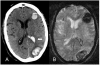

Amyloidosis comprises a rare spectrum of protein deposition diseases that diffusely or focally affect any organ. Amyloid's variable clinical presentation and nonspecific disease course often cause it to evade early diagnosis. This pictorial essay aims to familiarize radiologists with the pathophysiology of amyloidosis, to describe the basic classifications of amyloidosis, and to use multimodality imaging to illustrate its varied appearance throughout the body. This review highlights the diagnostic challenge of interpreting radiographic studies in patients with hematologic malignancies and concurrent amyloidosis. Radiologists should consider amyloid in chronically ill patients or patients with hematologic malignancies who have unusual/unexpected imaging findings.